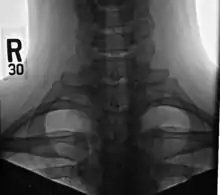

Cervical rib

A cervical rib in humans is an extra rib which arises from the seventh cervical vertebra. Their presence is a congenital abnormality located above the normal first rib. A cervical rib is estimated to occur in 0.2% (1 in 500 people)[2] to 0.5%[3] of the population.[4] People may have a cervical rib on the right, left or both sides.[5]

Diagnosis

On imaging, cervical ribs can be distinguished because their transverse processes are directed inferolaterally, whereas those of the adjacent thoracic spine are directed anterolaterally.[10]